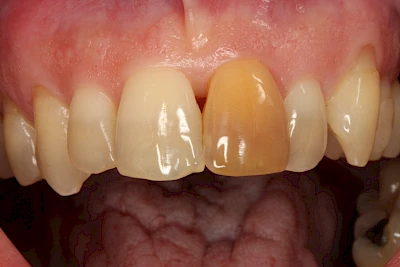

- Durch Blutabbauprodukte, weil der Zahnnerv abgestorben (einzelner Zahn, dunkel-flächig)

Ist ein einzelner Zahn deutlich dunkler als die Nachbarzähne kann das ein Zeichen sein, dass der Nerv abgestorben ist. Unter Umständen wurde bereits eine Wurzelkanalbehandlung vom Zahnarzt durchgeführt. Eine Abklärung durch den Zahnarzt ist in jedem Fall sinnvoll.